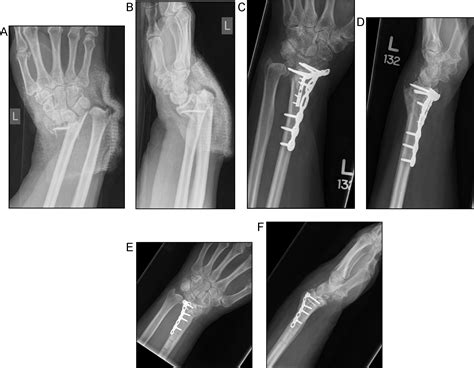

Surgical intervention is often necessary for displaced or unstable fractures. The most common surgical procedure for Orif Distal Radius fractures is open reduction and internal fixation (ORIF).

ORIF involves:

• Open Reduction: Surgical exposure of the fracture site to realign the bone fragments.

• Internal Fixation: Use of plates, screws, or pins to stabilize the fracture and promote healing.